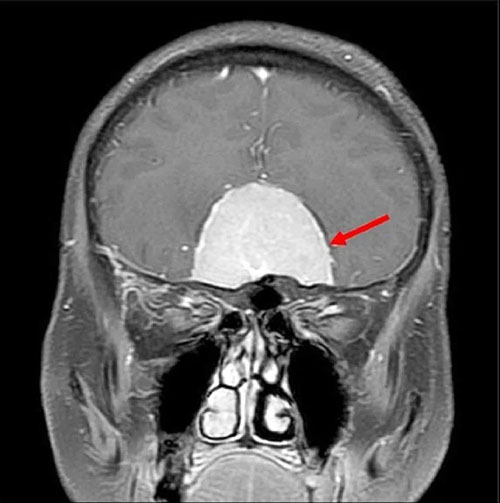

▲术前磁振扫描显示颅底巨大脑瘤(箭头处)